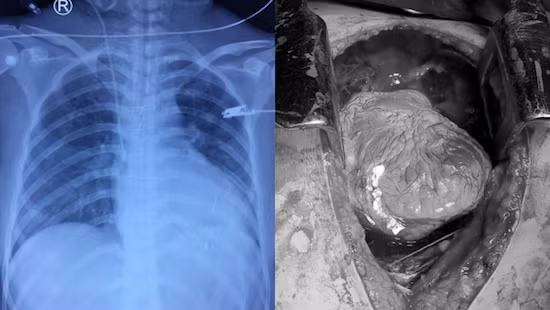

| Hình ảnh trái tim bị tổn thương của bệnh nhân |

Ngay khi mở ngực, các phẫu thuật viên Tim mạch – Lồng ngực phát hiện tim bệnh nhân bị chèn ép cấp do tràn máu màng tim lượng nhiều, khi mở màng ngoài tim, phát hiện vết thương tim thủng thất phải gây cắt đứt một nhánh bờ phải của động mạch vành phải và đang phun máu ồ ạt. Trong tình trạng ấy, các phẫu thuật viên vừa dùng tay bịt vết thương cầm máu tạm thời, vừa khâu lại vết thương tim.